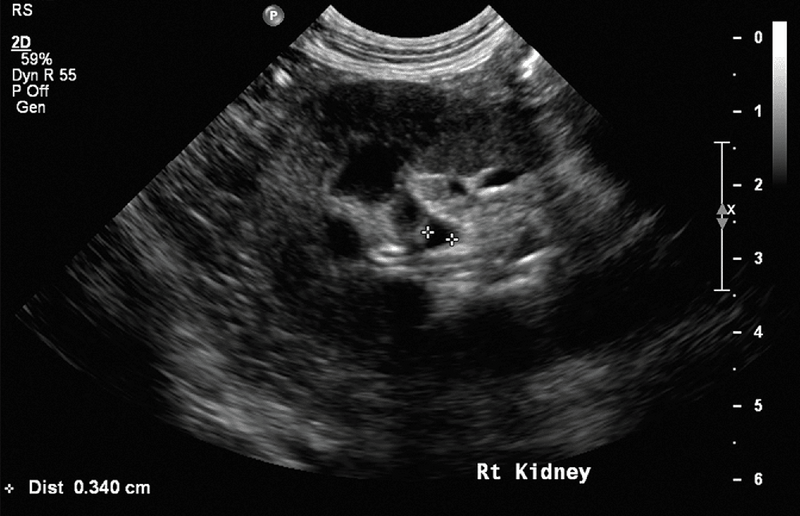

Mineralizacja

Dystroficzne odkładanie się substancji mineralnych w nefronach i śródmiąższu nerki może występować wtórnie do jej uszkodzenia i bywa trudne do odróżnienia od zwłóknienia nerek. Korelacja histologiczna jest ograniczona, przypuszcza się jednak, że mineralizacje (ryc. 11) najczęściej odpowiadają punktowym i/lub liniowym, hiperechogenicznym ogniskom w korze nerkowej, które są zazwyczaj zbyt małe, by powodować dystalny cień akustyczny.8 Hiperechogeniczne pasma w rdzeniu nerek, również uważane za przejaw mineralizacji i/lub zwłóknienia, obserwuje się w bardziej postępującej chorobie nerek.3 Tzw. objaw rąbka rdzeniowego, choć występuje zarówno u psów z przewlekłą niewydolnością nerek, jak i bez niej, był wcześniej łączony z możliwą mineralizacją nabłonka kanalików nerkowych oraz błony podstawnej u psów z nefropatią hiperkalcemiczną.9,20 Mineralizacja nerek może być nasilana przez przewlekłą hiperkalcemię wynikającą z podwyższonego stężenia parathormonu w reakcji na pogorszenie czynności nerek. Choć mineralizacja nerek może być wtórna do przewlekłej ich choroby, może również wynikać z chorób endokrynologicznych lub innych zaburzeń metabolicznych.8,17 Dodatkowo mineralizacja uchyłków nerkowych może stanowić przewlekłe następstwo wcześniejszego lub utrzymującego się odmiedniczkowego zapalenia nerek.

• Medium 1904

Ryc. 11. Obrazy w projekcji strzałkowej nerek psa. a) Prawa nerka ukazująca punktowe i liniowe ogniska hiperechogeniczne w korze, które mogą odpowiadać mineralizacji związanej z przewlekłą chorobą nerek. b) Lewa nerka ukazująca objaw rąbka, który wcześniej również wiązano z mineralizacją wtórną do nefropatii hiperkalcemicznej. Możliwy jest także obraz prawidłowy nerki.